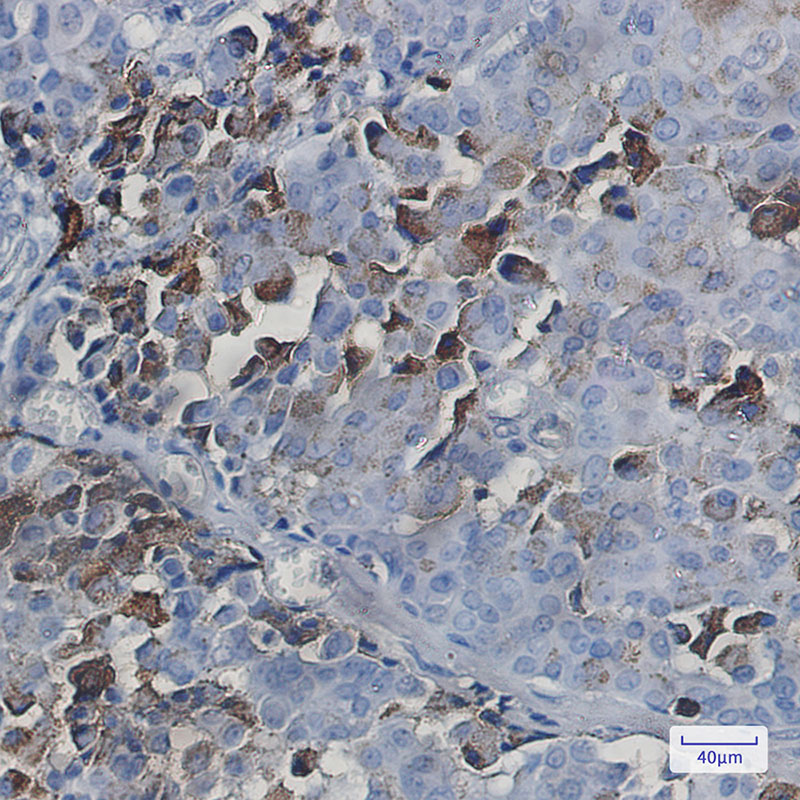

- Immunohistochemistry analysis of paraffin-embedded Human breast cancer tissue using NXF1 antibody. High-pressure and temperature Sodium Citrate pH 6.0 was used for antigen retrieval.